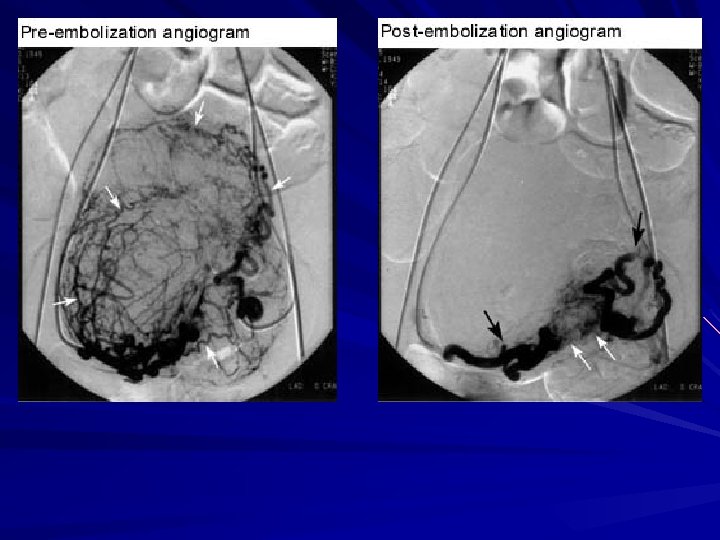

Uterine Fibroids UAE is a fundamentally different treatment for fibroids Minimally invasive Low complication rates Effective Repeatable if necessary Uses proved technique of embolization, available for more than 30 years

Uterine Artery Embolization Uterine artery embolization (UAE) as a primary form of therapy was reported by Ravina in 1995 16 patients were treated Polyvinyl alcohol particles used as embolic agent Mean FU 20 months Symptoms resolved in 11 of 16 patients 3 partially improved 2 failures (1 hysterectomy @ 6 weeks, 1 myomectomy @ 6 months Ravina et al. Lancet 1995

Uterine Artery Embolization Severe bleeding was controlled, even in women with large uteri and minimal initial volume reductions UAE reduced the average menstrual duration from 7. 6 to 5. 4 days 17 pregnancies were observed Major complications occurred in 1% of the cases Pron et al Fertility & Sterility, 2003